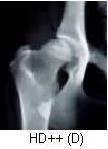

HD++ (grau D) - Displasia Moderada;

Por Norberg: * Cabeça do fêmur e acetábulo com incongruência nítida (sub-luxação);

* Angulos de Norberg entre 90 e 100 graus;

* Sinais de artrose bem evidentes;

Alterações: * Ossos espessos e irregulares;

* Dor à palpação e claudicação.

NÃO APTO À REPRODUÇÃO